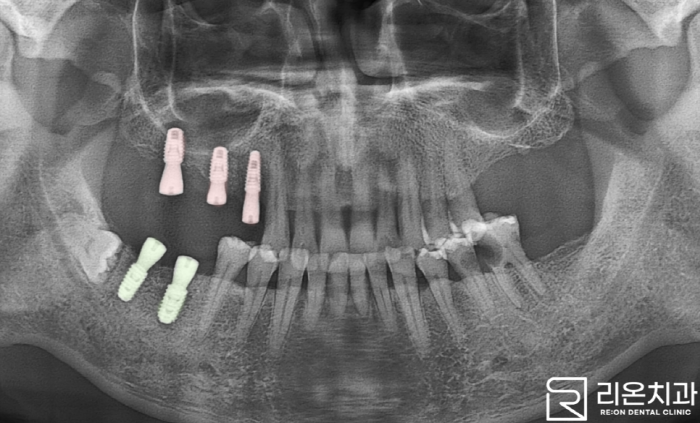

■ 3. 과정

리온 치과 에서 계획했던 것처럼 15, 46, 47번을 먼저 발치했으며 이후 Implant를 식립합니다.

앞서 말씀드렸듯이 위턱에 존재하는 maxillary sinus을 고려해야 되는데요,

픽스처를 단단히 지지해 주는 치조골이 부족할 경우,

상악동 거상술(Sinus Lift Surgery)을 이용해 골이식을 진행하게 됩니다. *위턱에서 상악동을 들어 올려 그 공간에 인공 뼈나 환자의 자가뼈를 이식하는 절차.

앞선 문제 확인을 위해 정밀한 3D-CT를 실행하여 뼈의 위치, 폭, 밀도 등을 확인하여 진행합니다.

확인 결과 이 케이스의 경우 골의 높이가 충분하다 판단하여,

수압거상(Hydraulic Sinus Lift)으로만 실행하게 되었습니다. *maxillary sinus과 자연치 뿌리 사이에 공간을 확보하여 픽스처를 식립하는 방법으로 골이식을 하지 않고 수압을 이용하여 상악동의 바닥을 들어 올리는 방식.

아래턱에 있는 47번의 경우 보통 옆에 매복되어 있는 사랑니를 발치하나,

매복니가 별다른 증세가 없으며 리온 치과 에서는 발치할 경우 오히려 주변 골 소실로 인해 47번 식립이 지연되거나 어려울 수 있다고 판단했습니다.

촬영일: 2023.11.17

이렇게 픽스처가 앞선 과정들을 통해 식립되었는데요,

치조골이 나사선 사이로 차올라 고정되는 대략 6~7개월의 기간을 기다린 뒤 보철을 체결합니다.

이 기간 동안 임시치아를 사용하게 되니 일상생활에서의 문제는 없습니다.